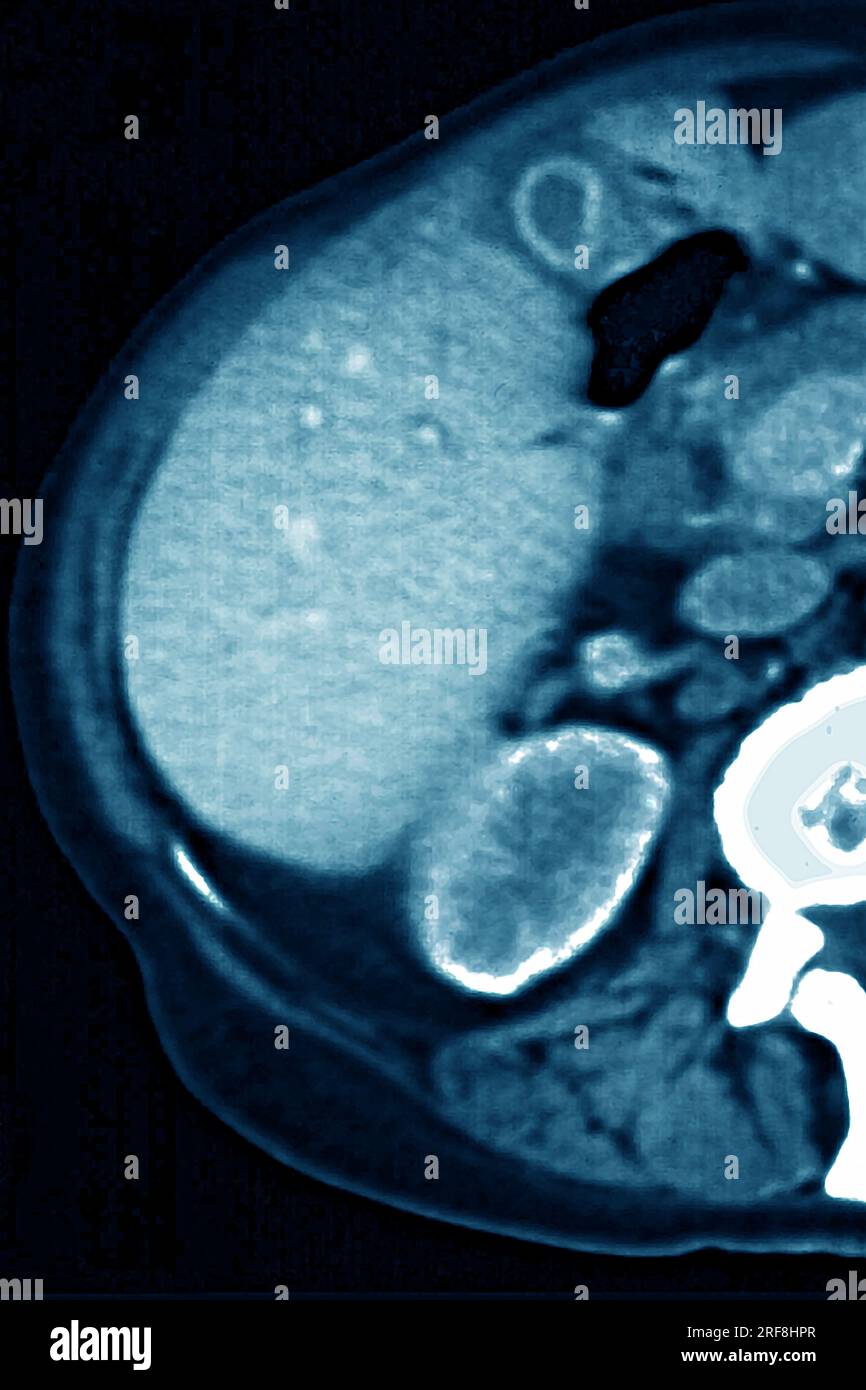

Lymphoma revealed by lymphadenopathy between the liver and the gallbladder. abdominal scan in radial section. Stock Photohttps://www.alamy.com/image-license-details/?v=1https://www.alamy.com/lymphoma-revealed-by-lymphadenopathy-between-the-liver-and-the-gallbladder-abdominal-scan-in-radial-section-image560141199.html

Lymphoma revealed by lymphadenopathy between the liver and the gallbladder. abdominal scan in radial section. Stock Photohttps://www.alamy.com/image-license-details/?v=1https://www.alamy.com/lymphoma-revealed-by-lymphadenopathy-between-the-liver-and-the-gallbladder-abdominal-scan-in-radial-section-image560141199.htmlRM2RF8HPR–Lymphoma revealed by lymphadenopathy between the liver and the gallbladder. abdominal scan in radial section.